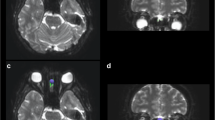

NBS of structural connectivity

NBS analysis revealed a single network of decreased structural connectivity in the hypos-PD group as compared with the HC group (t = 3.662, p < 0.01). The network comprised a total of 2 nodes, including the right medial orbitofrontal cortex (mOFC) and the left rectus (Fig. 2). In contrast, the norms-PD group did not show any alterations of structural connectivity when compared with HC and hypos-PD groups.

In this study, we comprehensively examined the whole brain for hyposmia-associated WM changes in newly diagnosed PDs using TBSS, graph-theoretical and network-based analyses. Findings from our study revealed no significant regional changes as reflected by FA and MD but observable alterations at the network level as evidenced by reduced global and local efficiency in the early disease stages of PD. Hypos-PD patients additionally showed reduced connectivity within a single network that comprised the right mOFC and left rectus, compared with HCs.

Prior studies have observed FA reduction in the rectus18 and reduced functional activation and connectivity in the OFC and rectus regions in hypos-PD patients14. In this study, we demonstrated that structural connection between these two regions was disrupted in early hypos-PD patients, thereby providing further support to the literature. Reduced connectivity strength between the right mOFC and left rectus also showed significant power to differentiate hypos-PD patients from HCs. Unlike previous functional MRI studies that showed widespread alterations of functional connectivity in PD patients with hyposmia14,27,28, we only observed a single microstructural network breakdown in our DT study. The explanations could be first, the use of different imaging modalities and different disease stages of patients in our study and in other studies. According to a recent report, subtle structural network alterations but more prominent functional network reduction were found in early PD29. Also, findings from prior neuroimaging studies in olfactory dysfunction in PD (see Supplementary Table S1) indicated that in general, studies using functional imaging, including PET and SPECT, observed more significant brain areas relating to olfactory impairment, compared with structural imaging studies. Therefore, it would be reasonable to expect less salient change in WM structural networks in early PD patients with hyposmia. Second, different imaging analytical approaches may also account for discrepant findings. For instance, ROI-based studies only examined few pre-selected brain regions and hence usually do not apply correction methods for multiple comparisons. In contrast, studies examining the whole brain are deemed to correction for multiple comparisons. Different analytical approaches and correction methods for multiple comparisons have different operations to determine statistical significance, which is likely to lead to different results. Nonetheless, hyposmia-related brain regions found in our current study on early and de novo PD were in good agreement with previous observations14,18,19,30,31.

We show for the first time that in addition to the breakdown of the efficiency of information transfer and resistance to local neural deficits, a subnetwork connecting the right mOFC and left rectus was disrupted, whereas no regional changes were observed in early hypos-PD patients. By examining whole-brain regional and network topology of early PD patients, our findings suggest that compromised connectivity of the right mOFC and left rectus uniquely differentiates hypos-PD patients from HCs, and thus serve as a potential biomarker for hyposmia in early PD. Future studies may expand on this work by assessing whether alterations of this subnetwork can predict cognitive decline in hypos-PD patients.